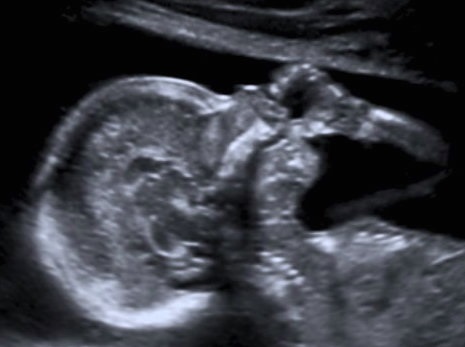

desde en vientre materno, el bebé ya se chupa el dedo

Primero que nada debemos saber que muchos bebés y niños se chupan los dedos pulgares incluso cuando todavía están en el vientre materno. Es fisiológico y es un signo de madurez de su desarrollo psicomotor que puede considerarse normal hasta cierta edad.

A partir de la decimosegunda semana de gestación, el bebé empieza a realizar este gesto y este hecho se ha podido confirmar cuando se realiza una ecografía durante el control prenatal. Cuando el bebé nace y activa este reflejo, se pueden producir dos tipos de succión: